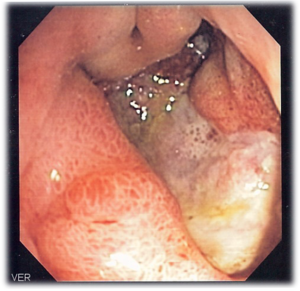

وقد أصبح بالإمكان حديثاً علاج معظم المضاعفات تنظيرياً، مثل وضع مشابيك (كليبسات) agraffe معدنية على الوعاء النازف عبر المنظار الضوئي أو حقن مواد مصلِّبة تغلق الوعاء النازف. وكذلك يمكن إجراء توسيع للبواب المسدود بوساطة بالون خاص عبر المنظار أيضاً. وعلى الرغم من أنه أصبح من النادر إحالة مريض قرحة العفج إلى الجراحة، إلا أنه لا يمكن الاستغناء عنها لعلاج معظم حالات الانثقاب.

كان التصوير بالباريوم (وهو مادة سائلة بيضاء معدنية يتناولها المريض عن طريق الفم ويظهر انعكاسها بالتصوير بأشعة إكس Xـrays) هو الإجراء المتبع في تشخيص القرحة، إذ يعكس وجود ما يسمى العش القرحي، وهو تجمع للباريوم في حفرة القرحة بشكل دائرة. ولكن في أوائل السبعينيات بدأ استخدام التشخيص بالمنظار الضوئي وهو أنبوب رفيع مرن مؤلف من أكثر من 40ألف ليف زجاجي كلها فائقة النقاوة مع كاميرا في رأس الأنبوب. يدخل المنظار من الفم على الريق بعد صيام عن الطعام يدوم نحو 8ساعات وتتم دراسة المري والمعدة والعفج. وميزة هذه الطريقة، إضافة إلى أنها تجرى بالتخدير الموضعي، أنها تمكن من الرؤية المباشرة للقرحة وأخذ خزعات منها لنفي السرطان ومعالجة بعض مضاعفاتها من خلال المنظار كالنزف والانسداد. وقد بات ممكناً توثيق النتائج documents بالأجهزة المتطورة (منظار فيديو) على شريط فيديو أو أخذ صورة مباشرة. وثمة اختبارات أخرى تستخدم في تحديد وجود جرثومة الملوية البوابية وهي: الفحص بالمجهر لخزعة من المعدة تؤخذ في أثناء التنظير ورؤية الجرثومة مباشرة، أو فحص هذه الخزعة على وسط جيلاتيني مكون من مادة اليوريا، ففي حال وجود الجرثومة تحلل هذه المادة وتغير لونها وتسمى هذه الطريقة اختبار اليوريا urea test. تقدر حساسية sensitivity هذا الفحص بنحو 90%، ويعطي جواباً سريعاً في نصف ساعة. وهناك اختبار النَفَس breath test الذي تقدر حساسيته أيضاً بنحو 90%، وهو يكشف عن وجود الجرثومة بالنفخ في كيس مغلق بعد تناول سائل من دون طعم يحوي على كربون مشع يشكل جزءاً من مادة اليوريا التي تتحلل في حال وجود الجرثوم في المعدة وتخرج ذرة الكربون بشكل ثاني أكسيد الكربون في عينة النفس. وميزة هذا التحليل أنه يجرى من دون حاجة للتنظير ويفيد عادة في المتابعة بعد المعالجة للتأكد من القضاء على الجرثوم. وأخيراً تحليل الدم لكشف أضداد الجرثوم والذي لايميز عادة بين الإصابة السابقة والحالية مما يفقده فعاليته.